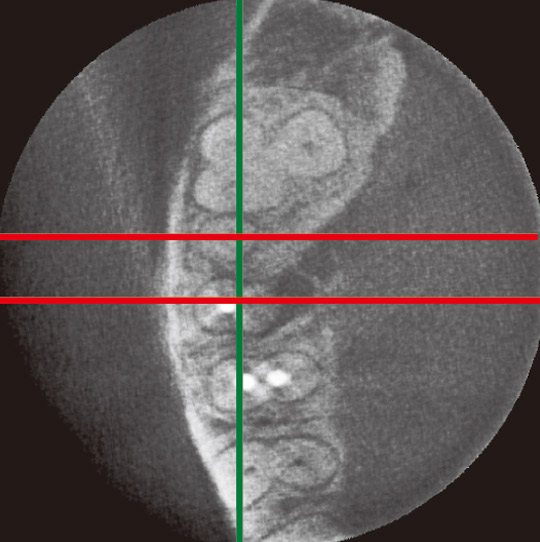

図5は567のクラウンに2次う蝕を認め再治療が必要になった症例である。

まずはデンタルのみの所見から、歯内療法を行うかどうかを判断してから、CBCT像を見てほしい。デンタルからは明らかな根尖病変を認めなかったが、患者にデンタルの感度を伝えたうえで将来の急発率や再治療の可能性、CBCTの被曝量を伝えたところ、CBCTでの診査を希望した。

その結果、5 、6 近心根、遠心根に根尖病変を認め、再治療を行うことになった。

この症例のように、CBCTは失活歯の再修復治療を行う際、再歯内療法を行うかどうかの判断に影響を及ぼし、治療結果も変える可能性がある。

図5a、b 4567に2次う蝕があり再修復を行う。デンタルでは根尖病変を認めず、歯内療法を行うべきか迷う。

図5c 3DXによる水平断。

図5d 5の前頭断。根尖病変を認める。

図5e 6近心根の前頭断。根尖病変を認める。

図5f 6遠心根の前頭断。根尖病変を認める。

図5g 矢状断。5 6近心根、遠心根に根尖病変を認める。再治療を行うことになった。